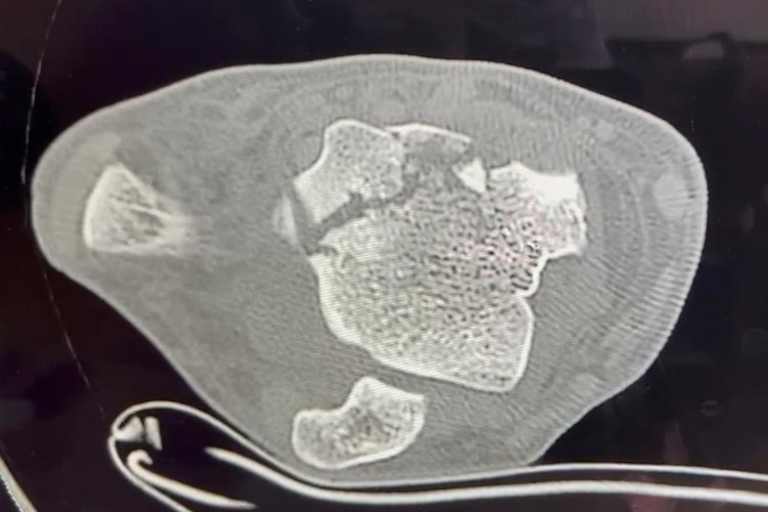

Allerdings tauchte Bondi am vergangenen Wochenende in Le Mans mit Gehhilfen und einem Gips am linken Unterschenkel auf. Grund hierfür ist ein mehrfach gebrochener Knöchel nach einem Trainingssturz.

"Nach meinem Sturz wurde mir ein Gips verpasst, damit sich der Knöchel so gut wie möglich vor dem ersten offiziellen Test der Frauen-Weltmeisterschaft in Cremona festigen kann", verriet Bondi. "Wenn die Prognose zutrifft, werde ich bis zum ersten Rennen der Weltmeisterschaft wieder fit sein. Mein Ziel ist, bei Saisonstart wieder in Bestform zu sein!"